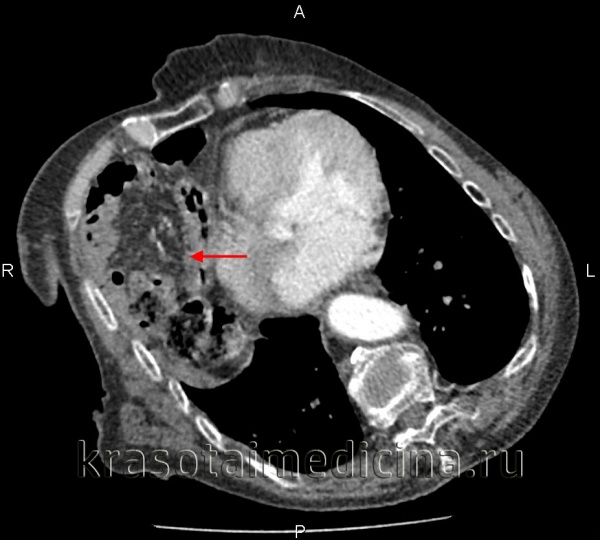

- Лучевая диагностика. Выполняется рентгенография и КТ грудной полости, КТ брюшной полости. Выявить разрыв на рентгенограмме можно только при пролапсе органов пищеварения в область грудной клетки. Для уточнения локализации травматического дефекта грудобрюшной перегородки, дифференциальной диагностики травмы и релаксации органа осуществляется контрастная рентгенография желудка либо ирригография. Просматривается желудок или петли кишечника в левой половине грудной клетки, определяется смещение пищевода.

КТ органов грудной клетки/брюшной полости. Травматический дефект в передних отделах диафрагмы справа с эвентрацией кишечника, сальника, кровеносных сосудов в грудную полость

- Ультразвуковое исследование.УЗИ ОБП и УЗИ плевральной полости даёт возможность подтвердить наличие диафрагмального дефекта, смещение ОБП, наличие свободной жидкости в обеих полостях. Наблюдается высокое стояние одного из куполов диафрагмы. Левосторонний разрыв сопровождается разъединением плевральных листков с появлением неоднородного содержимого между ними. При правостороннем дефекте обнаруживается необычно высокое расположение печени – её верхний край может находиться на уровне второго ребра.